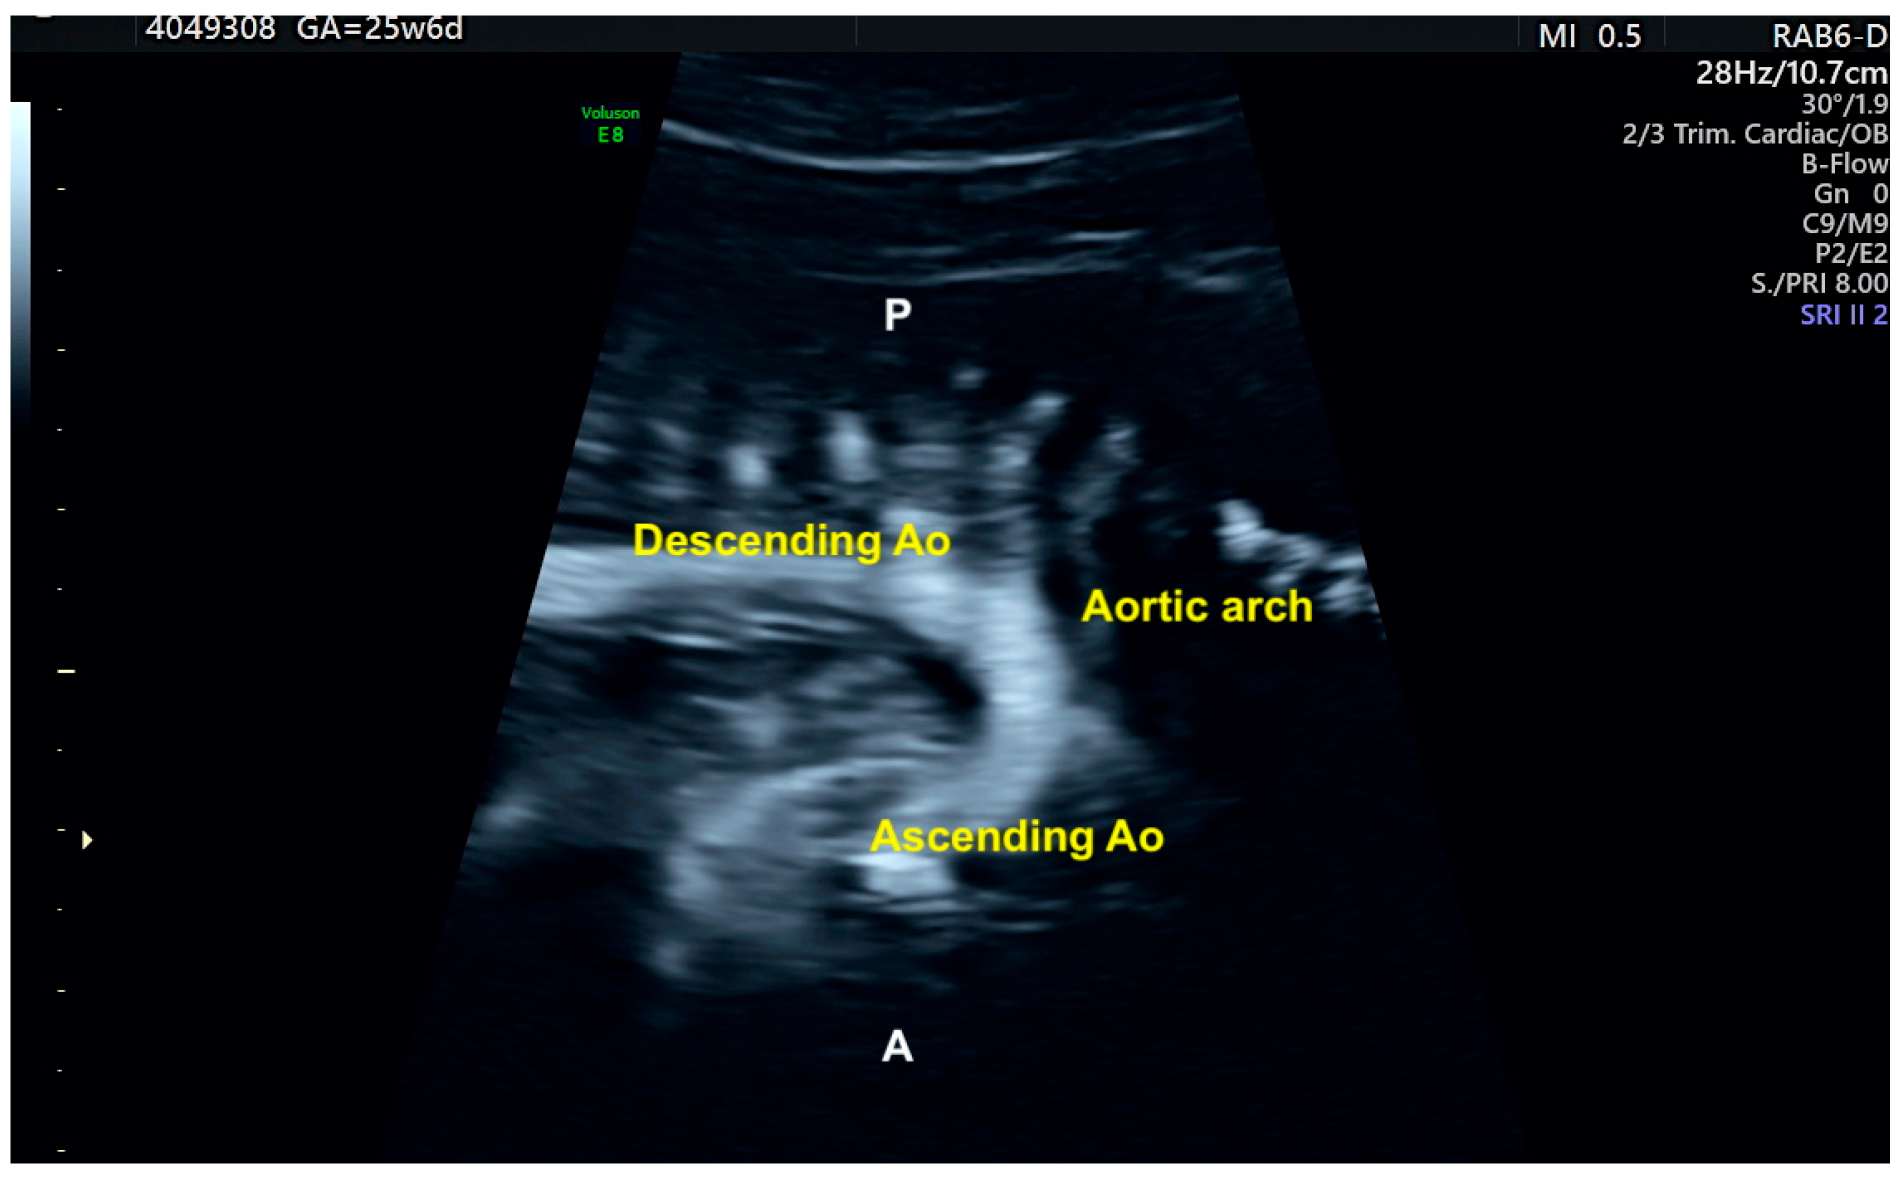

11. Anomalous Venous Return

12. Right Aortic Arch